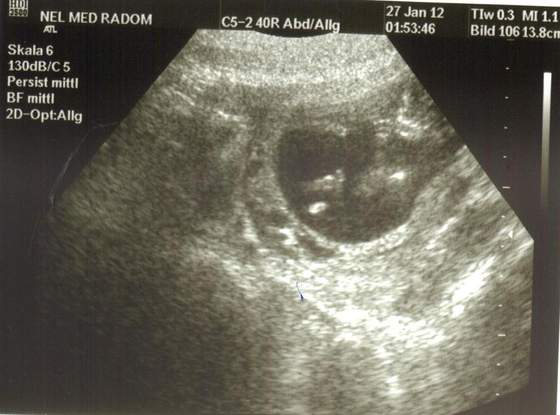

pamelcia ja miałam w 11 tyg przez brzuszek usg i jak widać niżej w sygnaturce ślicznie wszystko było widać :)